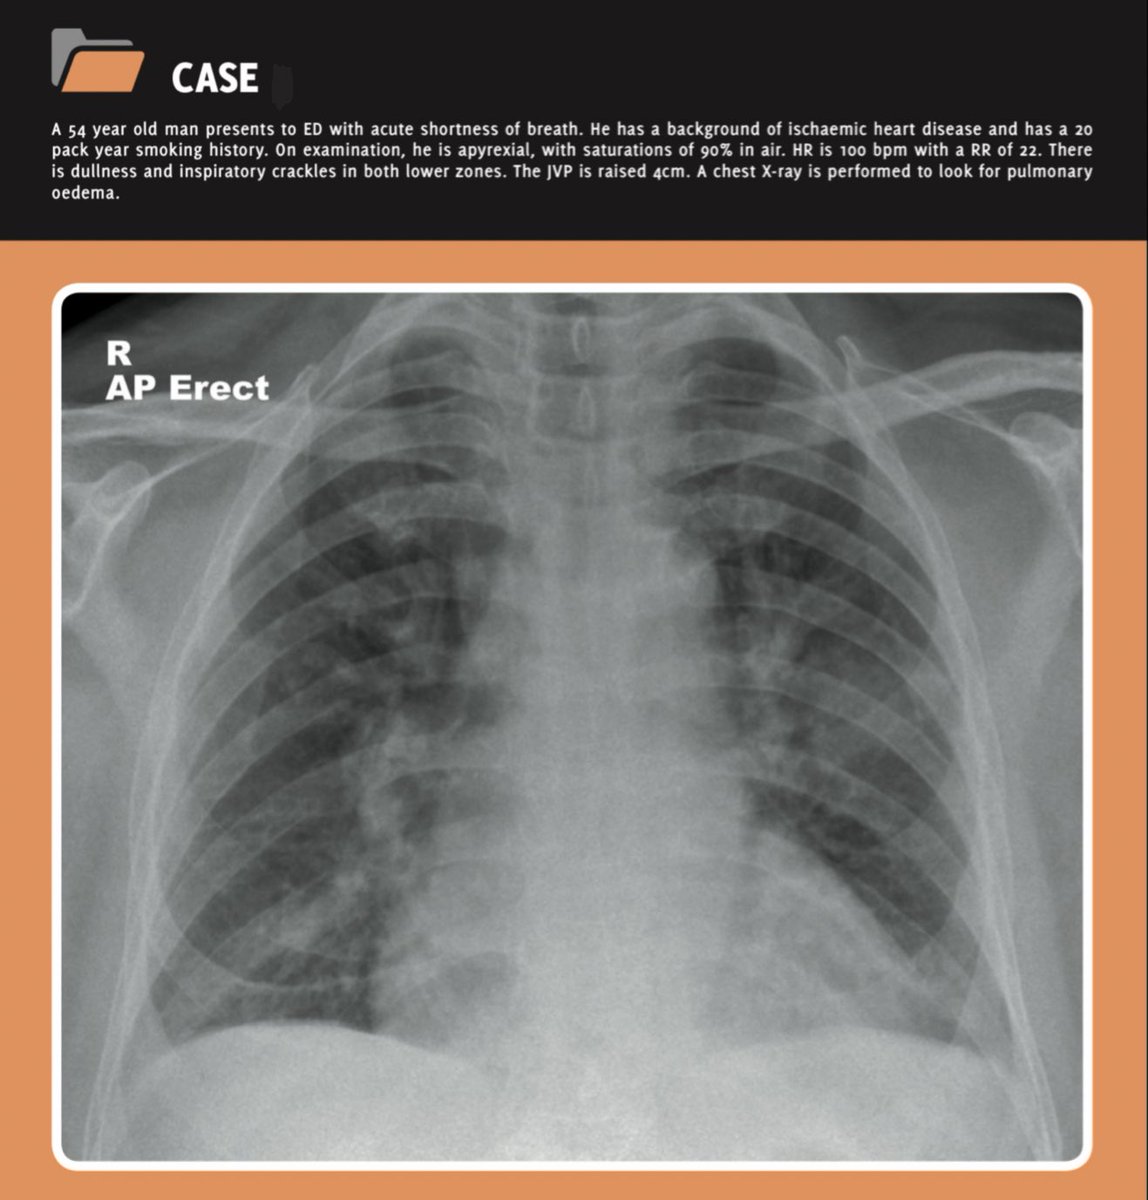

@world_of_med1 Bilateral lower zone opacities suggestive of pulmonary congestion/oedema, Possible cardiomegaly (or may be due to the view AP the heart appear enlarged), No clear pneumothorax or localized consolidation

and Vascular congestion visible